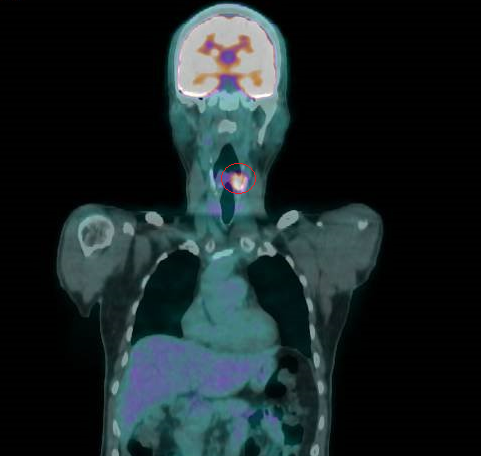

▲正子攝影顯示曾先生的下咽癌再度復發(紅圈處)。(圖╱彰化醫院提供)

許嘉方說,過了3年曾先生復發了,同位置的腫瘤2.1公分,也是2期,經評估不適宜再進行放療及化療,只得進行全喉切除,連同聲帶一併切除,在頸部開個永久氣切孔呼吸,讓口腔只用於進食,也就是飲食及呼吸分開,至於聲音部分,使用人工發聲器。